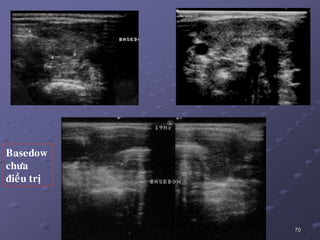

Basedow chöa ñieàu trò

ñieàu trò

68 1.1/. Basedow:  SAcoù 2 kieåu hình aûnh: _ Taêng saûn lan toaû ñoàng nhaát vôùi vaøi vuøng maïch maùu daõn . _ 86 % TG khoâng ñoàng nhaát khoâng toå chöùc hoaù, echo keùm gioáng nhö vieâm gíap hay hình aûnh nhaân giaû.  Ño ñaït theå tích tuyeán giaùp raát caàn thieát sau phaãu thuaät caét giaùp (taùi phaùt 20%), khi coù chæ ñònh ÑT baèng ioát phoùng xaï.  Suy giaùp sau phaãu thuaät 1%, sau ÑT ioát phoùng xaï25%.  Keát hôïp vôùi K chieám 0,3 – 16,6%, daïng nhuù >> daïng nang.

71 SA duøng ñaùnhgiaù söï ñaùp öùng ñieàu trò vaø tieân löôïng khaû naêng taùi phaùt.